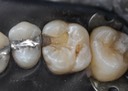

Joe Cha #20 amalgam removal